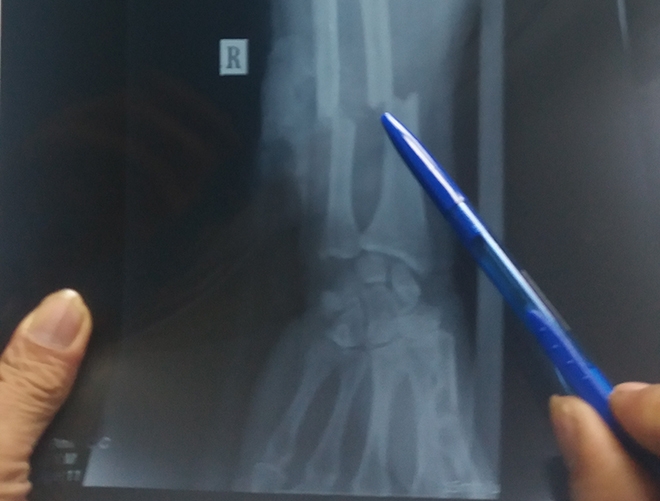

| Hình ảnh chụp X-quang cho thấy cẳng tay người đàn ông bị đứt lìa.(Nguồn ảnh: Vnexpress). |

Trao đổi trên báo Vnexpress, bác sĩ Nguyễn Hồng Hà, Bệnh viện Nhân dân Gia Định cho biết, nạn nhân được đưa vào viện cấp cứu chiều cùng ngày trong tình trạng mất máu nhiều nhưng vẫn còn tỉnh táo. Ngoài cẳng tay phải gần như đứt lìa, người đàn ông còn bị thương lộ xương bánh chè gối trái, đứt bán phần cơ rộng đùi trái.